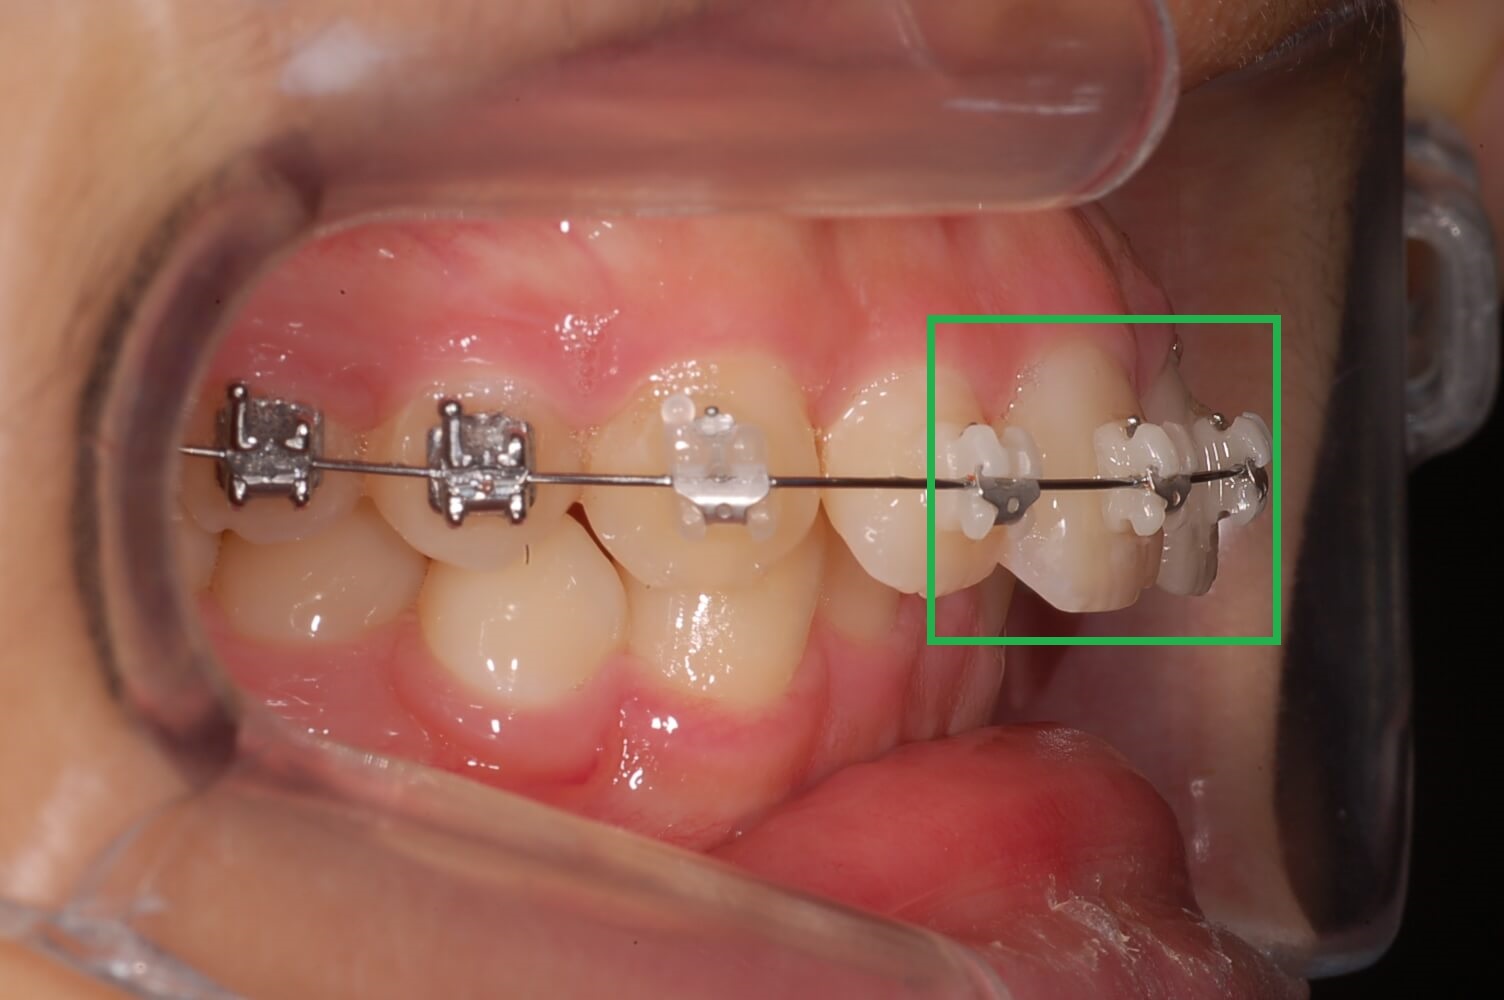

저는 치아가 자유로이 움직인다는 것을 처음 알았습니다. 그리고 복원력이 있다는 것도 알게 되었는데요. 사진에서 보듯이 어금니가 옆으로 누워있습니다.

위, 아래 어금니가 모두 그렇는데 아래 어금니는 브라켓 설치로 힘을 주어 잡아당기고 있고 윗 어금니는 스크류를 박고 고무줄(체인)로 잡아당기고 있습니다.

▼ 아래 어금니 블라켓으로 고정후 힘을 주어 당기고 있는 모습

▼ 윗 어금니는 스크루를 박고 체인으로 묶어서 한 단계씩 줄여나가면서 이동시킴.